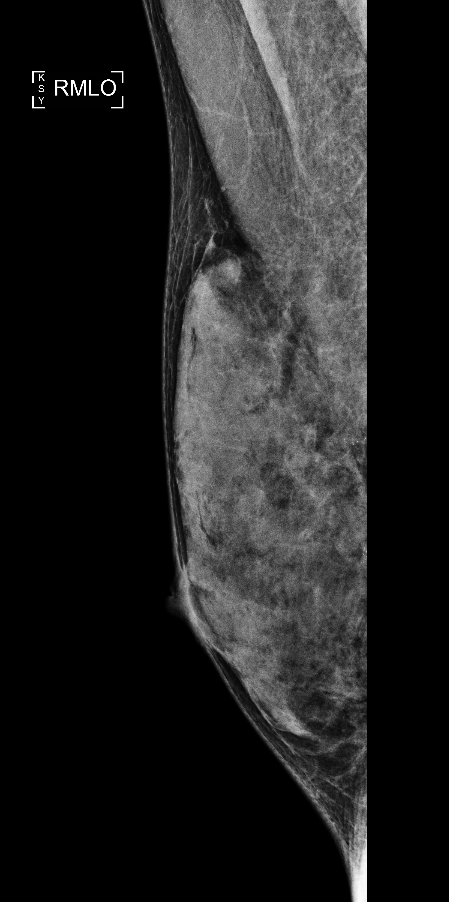

보통 유방 엑스레이 촬영을 할 때 지방이 많은 유방은 어둡게 보입니다. 그런데 치밀유방은 단단한 조직이 많아서 엑스레이 사진이 하얗게 나옵니다. 그런데 문제는 암과 같은 종양도 하얗게 보이기 때문에, 암이 있어도 잘 보이지 않을 수 있다는 점입니다. 그래서 치밀유방이 있는 사람들은 암을 찾기 어려울 수 있어서 주의가 필요합니다.

치밀유방은 유방 촬영(엑스레이) 사진에서 하얗게 보입니다. 그런데 암과 같은 종양도 하얗게 보이기 때문에, 두 개를 구별하기가 어렵습니다. 이는 마치 눈 덮인 들판에서 하얀 토끼를 찾는 것과 비슷합니다. 그래서 치밀유방이 있는 사람들은 암을 조기에 발견하기가 어려울 수 있습니다.

유방 촬영술은 여전히 기본적인 검진 방법입니다. 이 검사는 엑스레이를 사용해서 유방의 모습을 찍습니다. 하지만 치밀유방이 있는 경우 암 발견이 어려울 수 있으므로 추가적인 검사를 함께 하는 것이 좋습니다.